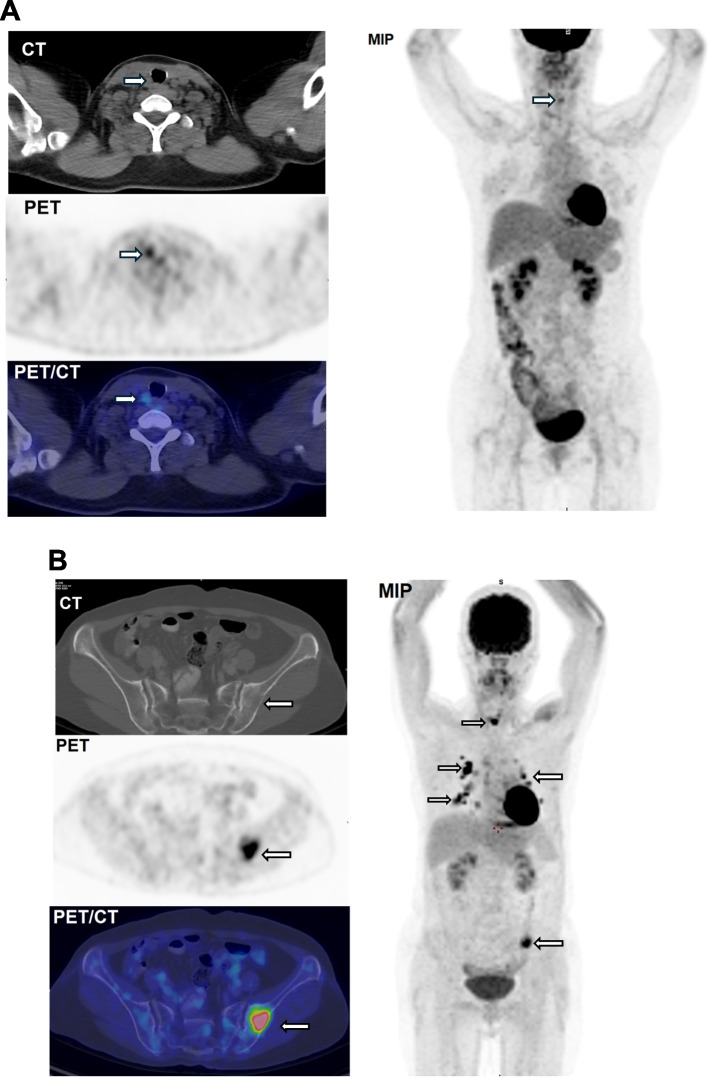

Methods: Post-operative DTC patients with TENIS syndrome were collected in the department of nuclear medicine, Hospital 108 from 2019 to 2023. Patients underwent [18F]FDG PET/CT with standard protocol following EANM guideline for tumor imaging version 2.0. The qualitative [18F]FDG PET/CT imaging characteristics were classified into three categories: (i) negative [18F]FDG PET/CT, (ii) minimal [18F]FDG PET/CT volume of lesions, (iii) extensive [18F]FDG PET/CT volume of lesions. Progression-free survival (PFS) and overall survival (OS) were the end point of the study. The prognosis of qualitative [18F]FDG PET/CT in predicting PFS and OS was illustrated by Kaplan-Meier survival analysis. The independent factors predicting PFS and OS were determined by univariate and multivariate analysis using logistic regression.

Results: There were 164 consecutive patients, 51.2% female and 48.8% female. The most common histopathological type was papillary accounting for 91.5%. The median time of follow-up was 33.3 months, (range 6.57 - 82.5). There was 70 (36.6%) progressions and 12 (7.35%) deaths. Negative [18F]FDG PET/CT uptake patients had median PFS with median 57.1 months which was higher than that of minimal category (46.2 months), and extensive category (37.6 months) (p < 0,001). 1-year OS and 5-year OS in extensive PET/CT category was 97.8% and 86.2% respectively which were significantly lower than that of negative and minimal categories (p = 0.053). In multivariate analysis, age at the time of diagnosis, pulmonary, bone metastases and extensive [18F]FDG PET/CT volume of lesions were the independent factor predicting PFS. Bone metastasis was only the factor could predict OS in multivariate analysis.